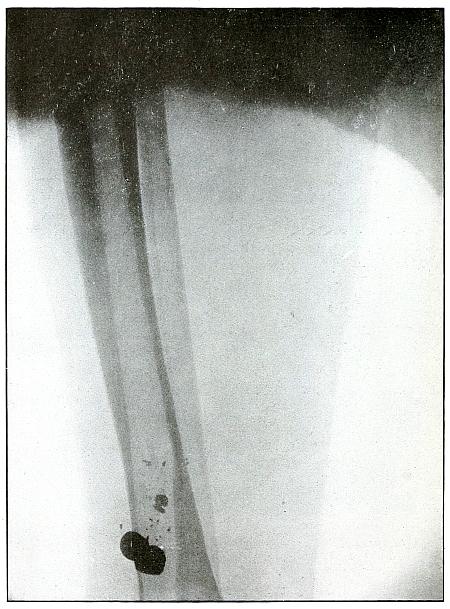

| 73. |

Gunshot wound, heel |

156 |

| 74. |

Gunshot wound, heel |

158 |